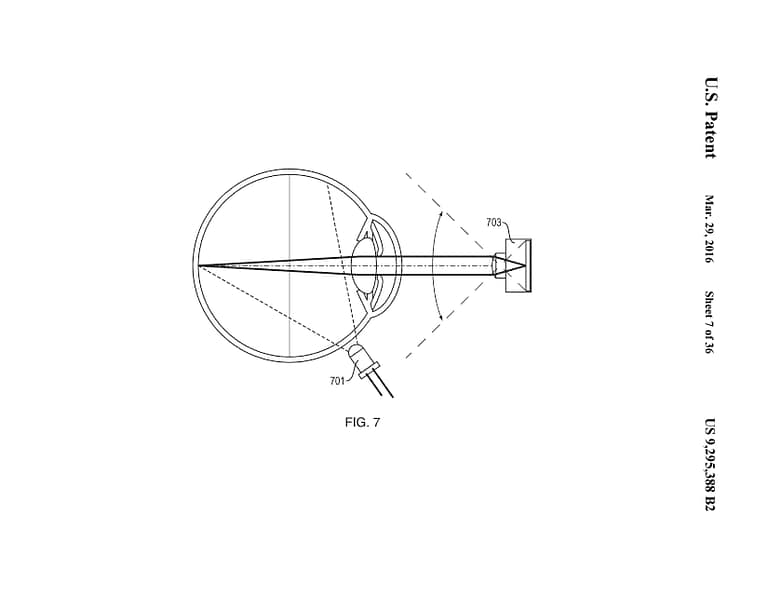

This invention comprises an apparatus for retinal self-imaging. Visual stimuli help the user self-align his eye with a camera. Bi-ocular coupling induces the test eye to rotate into different positions. As the test eye rotates, a video is captured of different areas of the retina. Computational photography methods process this video into a mosaiced image of a large area of the retina. An LED is pressed against the skin near the eye, to provide indirect, diffuse illumination of the retina. The camera has a wide field of view and can image part of the retina even when the eye is off-axis (when the eye’s pupillary axis and cameras optical axis are not aligned). Alternately, the retina is illuminated directly through the pupil, and different parts of a large lens are used to image different parts of the retina. Alternately, a plenoptic camera is used for retinal imaging.

In an initial alignment step, the imaging device displays real-time visual feedback to one eye (the stimulus eye) of a user. The visual feedback is indicative of (i) the pupillary axis of the user’s eye that is being imaged (the test eye) and (ii) the optical axis of the device’s camera. For example, an LCD in the device may display visual feedback that comprises a circle representative of the optic disc of the test eye (which serves as an approximate indication of the pupillary axis) and a square indicative of the center of the camera (which serves as an approximate indication of the optical axis of the camera). This real-time visual feedback guides the user as the user changes direction of gaze in order to self-align the two axes. Once the two axes are aligned, the imaging device displays a video of moving visual stimuli to the stimulus eye. The user’s stimulus eye tracks this moving stimuli.

Due to bi-ocular coupling, the test eye moves (rotates) in a similar path. As the test eye rotates into different positions, a camera in the device captures multiple images of different portions of the retina of the test eye. Each of these images may capture only a small portion of the retina. These images are processed and stitched together to form an image of a large area of the retina. This large field of view (FOV) image of the retina can be displayed to the user in real-time. As the test eye rotates (while bi-ocularly coupled to the stimulus eye), the test eye moves into many rotational positions in which the test eye is “off-axis’ with respect to the camera. As used herein: (i) an eye is “off-axis’ with respect to a camera if the optical axis of the camera is not pointed at the pupil of the eye; and (ii) an eye is “on-axis’ with respect to a camera if the optical axis of the camera is pointed at the pupil of the eye. The camera has a wide FOV and thus can capture an image of at least a small part of the retina, even when the test eye is off-axis.